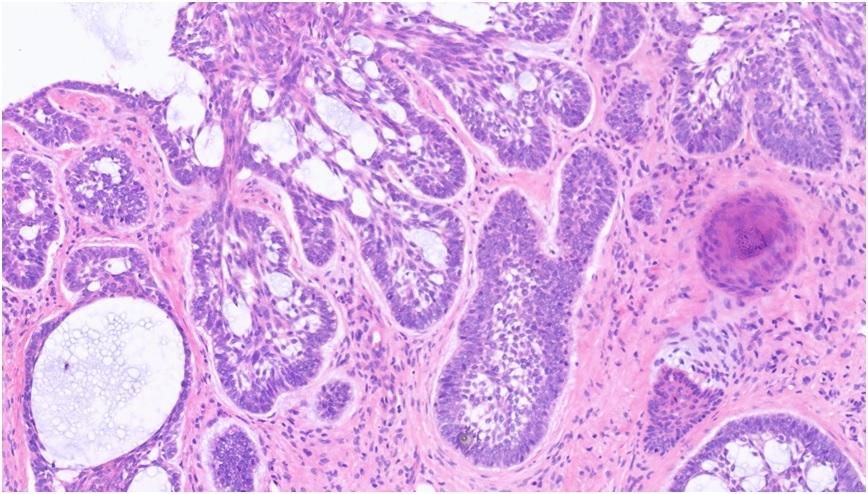

68M, 2VW - susp skin cancer. Lesion on tip of nose. Pigmented lesion with central regression, 4 mm in size. Hence removal of lesion using a 5 mm punch. DDx - naevus/melanoma. Sample 5 mm punch.